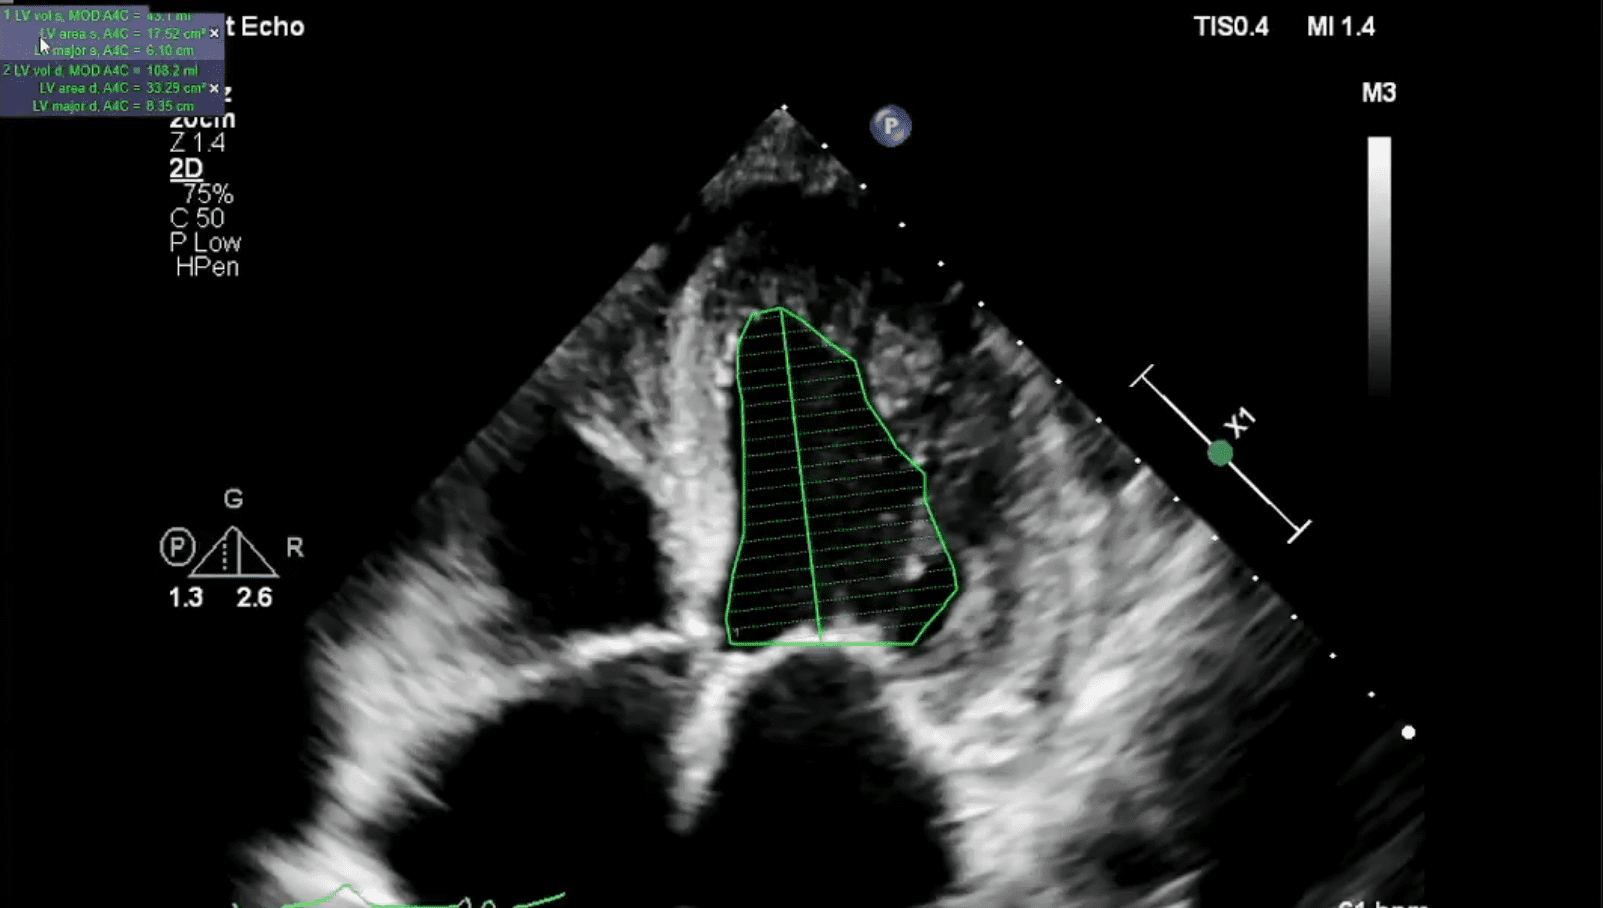

Echocardiogram showing severely reduced LVEF and dilated Left ventricle

Echocardiogram showing severely reduced LVEF and dilated Left ventricle Echo For Lvef An echocardiogram uses sound waves to create. Lvef is the fraction of chamber volume ejected in systole (stroke volume) in. Ejection fraction typically refers to the left side of the heart. Left ventricular ejection fraction (lvef) is one of the most commonly reported measures of left ventricular (lv) systolic function. Left ventricular ejection fraction (lvef) is a surrogate for left. Echo For Lvef.